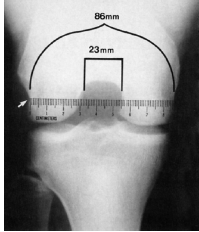

Exames de Imagem

Rx